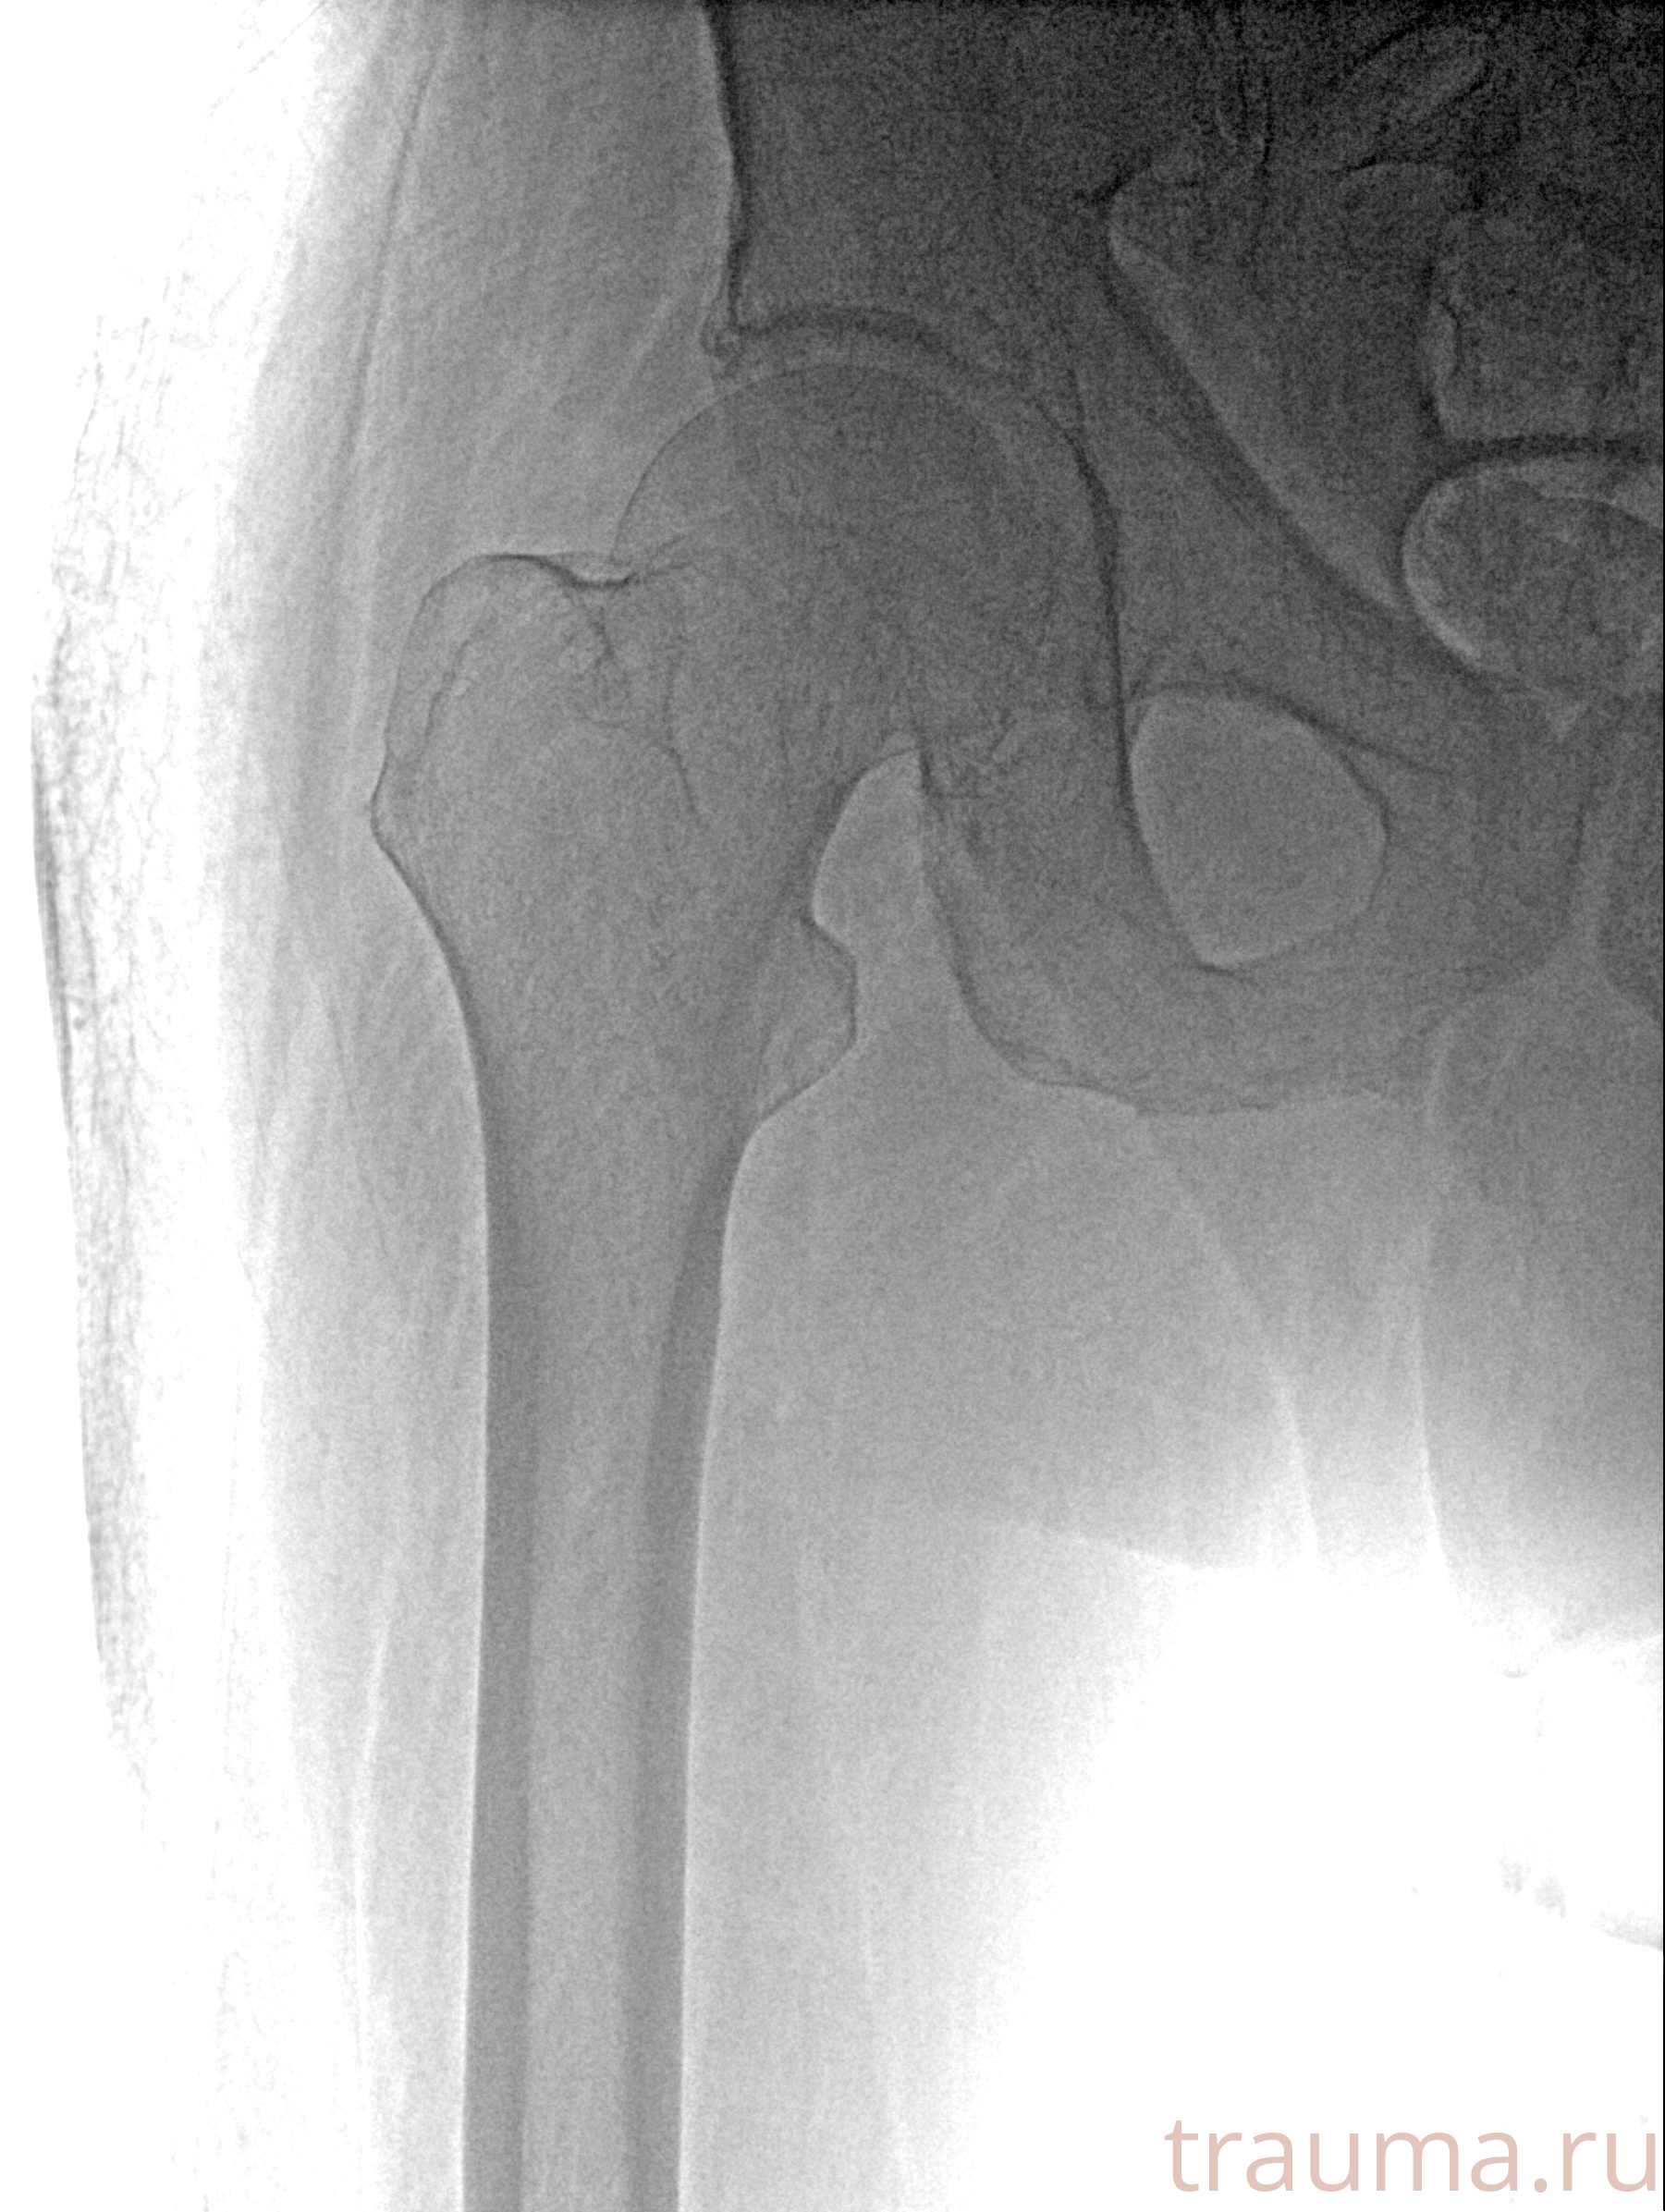

Рентгенограммы